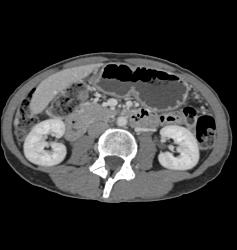

Diagnosis

Antral Carcinoma